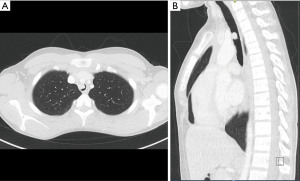

A 28-year-old female with a previous history of schwannoma resection, located at the ankle, presented with hemoptysis and dyspnea. A CT scan revealed a mid-tracheal endotracheal tumor with a maximum diameter of 13 mm and partial occlusion of the tracheal lumen with suspected invasion of the tracheal wall (Figure 5). No pathological lymph nodes or associated lung or bone lesions were noted. Spirometry revealed a flow volume loop indicative of central airway obstruction.